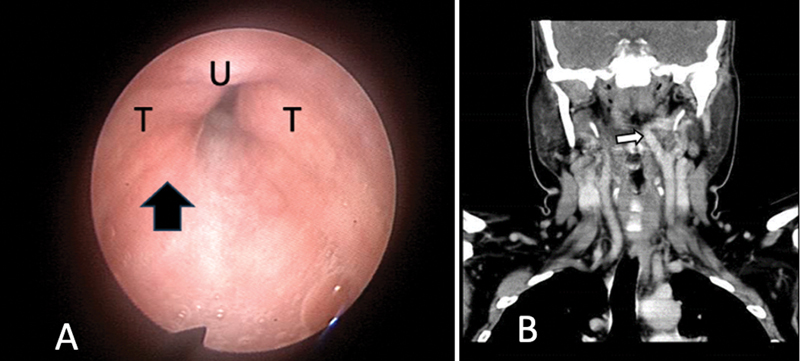

Obstructive sleep apnea (OSA) is often associated with reduced pharyngeal muscle tone and an anatomically narrowed pharyngeal airspace. We try to describe two cases with OSA that were diagnosed with vascular lesions during DISE: One of them was an aberrant internal carotid artery, and the second one was a glomus tumor. These anatomic anomalies contribute to airspace narrowing in these patients. These two cases describe an exciting presentation of sleep apnea and remind us of the importance of clinically recognizing vascular alterations to avoid damage during routine oropharyngeal procedures.